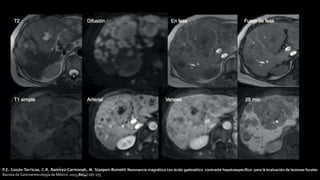

P.E. Cossio-Torricoa, C.R. Ramírez-Carmonab, M. Stoopen-Rometti Resonancia magnética con ácido gadoxético -contraste hepatoespecífico- para la evaluación de lesiones focales

Revista de Gastroenterología de México. 2015;80(4):267-275